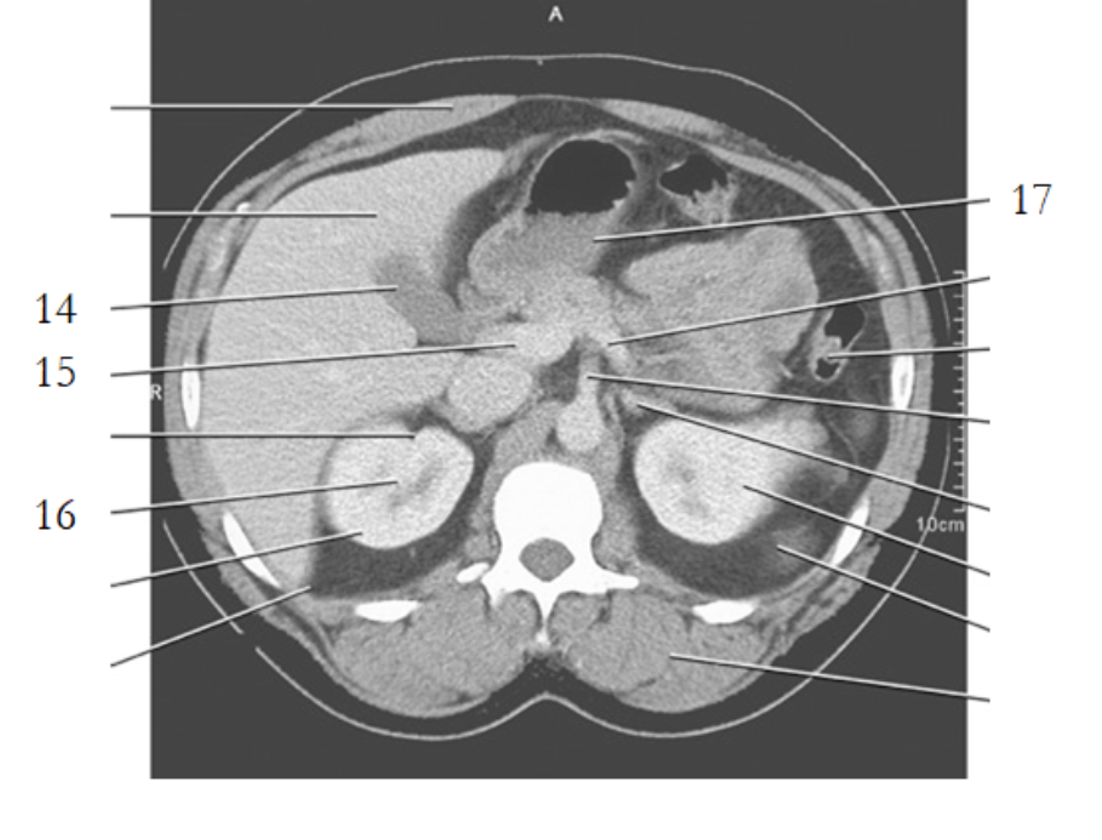

11

celiac axis

12

splenic artery

15

portal vein

20

aorta

24

19

left renal vein

1

liver

3

esophagus

stomach

spleen

9

crus of diaphragm

8

IVC

13

pancreas tail

16

kidney

14

gallbladder

4

left renal artery

small bowel

21

large bowel

25